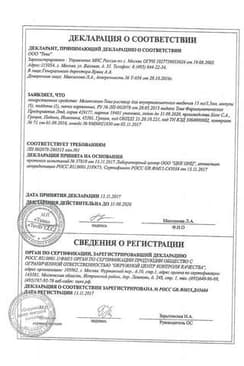

Сертификаты